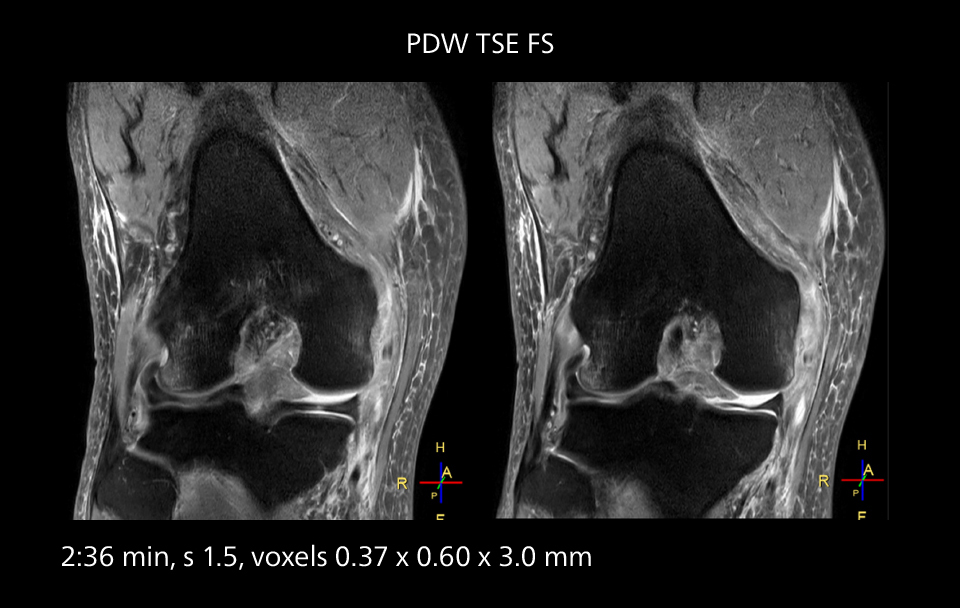

MRI of the knee

Images showing a posterior cruciate ligament (PCL) tear, a detached medial collateral ligament (MCL) on the tibial side and an intact anterior cruciate ligament (ACL). SmartPath to Elition X helped reduce scan time compared to previous imaging while maintaining resolution.

MRI of the knee

Images showing a posterior cruciate ligament (PCL) tear, a detached medial collateral ligament (MCL) on the tibial side and an intact anterior cruciate ligament (ACL). SmartPath to Elition X helped reduce scan time compared to previous imaging while maintaining resolution.